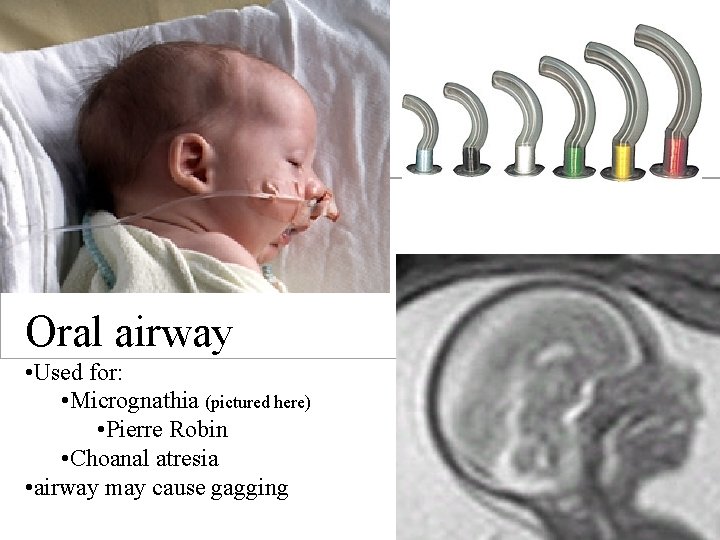

Oral airway • Used for: • Micrognathia (pictured here) • Pierre Robin • Choanal atresia • airway may cause gagging

Choanal Atresia Oral airway • Predict size measure from ear to corner of mouth • Placed right side up in the oropharynx (no need to rotate into place as with adult oral airways)